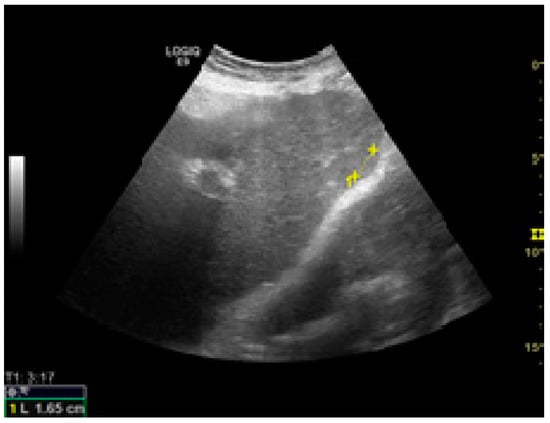

Among the factors associated with US detection performance, tumor size is one of the most important predictors, as larger nodules consistently lead to higher sensitivities. In one recent study, the sensitivity of US was 90%, 84%, 76%, and 65% for nodules larger than 4 cm, 3–4 cm, 2–3 cm, and 1–2 cm, respectively []. Infiltrative tumors are much more difficult to detect via US and are more often associated with surveillance failure [,]. In one study on 304 HCC patients who received regular surveillance with US and AFP, the failure rate was significantly higher for patients with infiltrative type tumors (57.1%) compared to nodular tumors (2.1%) []. Regarding echogenicity, isoechoic and faint hypo/hyperechoic lesions may escape a regular US evaluation (Figure 1 and Figure 2) [,]. The US visualization of nodules located in a deep or subcapsular position and/or near lung tissue (segments VII, VIII, and IVa) might be very difficult, or sometimes even impossible [,].

Figure 2.

Small isoechoic HCC, with a subcapsular location. US evaluation.